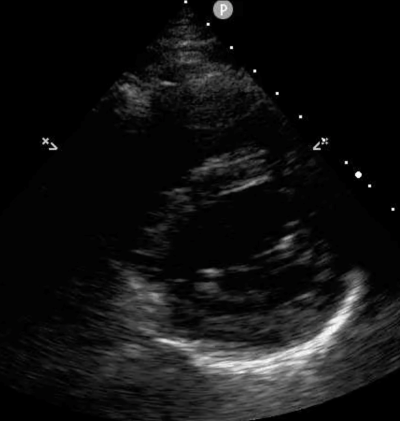

Orient the probe indicator to 10:30 o’clock (Figure 4) to achieve the PSL view (Figure 5).

Figure 5: PSL ultrasound image